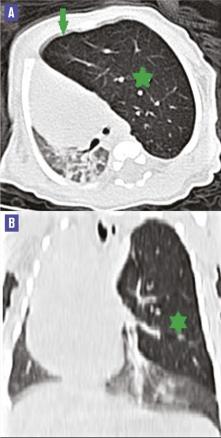

Ce nourrisson de 2 mois, issu d’un mariage non consanguin, né après une grossesse suivie et un accouchement médicalisé par voie basse, était admis aux urgences pour aggravation récente d’une dyspnée évoluant depuis la naissance. L’examen clinique notait une polypnée avec des signes de lutte et une déviation des bruits cardiaques à droite. Une radiographie standard et une tomodensitométrie (TDM) montraient une hyperclarté du lobe supérieur gauche associée à une déviation du médiastin vers la droite et une atélectasie du lobe inférieur gauche (figure ). Le diagnostic d’emphysème lobaire géant supérieur gauche a été retenu, et une lobectomie supérieure gauche a été réalisée. L’étude histologique de la pièce opératoire a confirmé le diagnostic. Dix-huit mois plus tard, l’enfant était asymptomatique.

La radiographie standard, souvent réalisée en première intention dans l’urgence, permet généralement de poser le diagnostic. Elle met en évidence une hyperclarté unilatérale refoulant le médiastin et des signes d’hyperinflation :2 horizontalisation des côtes, élargissement des espaces intercostaux, abaissement de la coupole diaphragmatique homolatérale, déviation controlatérale des structures médiastinales.

La TDM, réalisée en deuxième intention, permet de confirmer le diagnostic, de préciser la topographie, les caractéristiques lésionnelles ainsi que les complications et autres anomalies éventuellement associées.